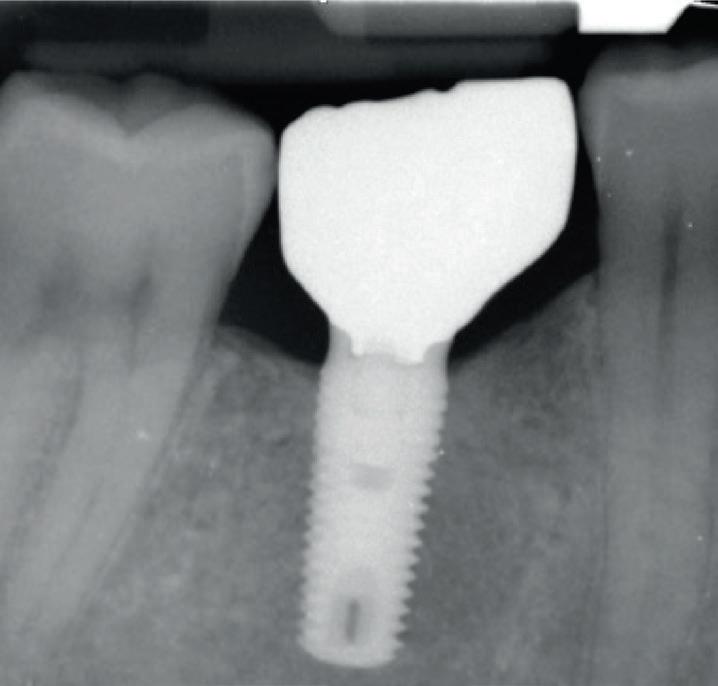

Each year, millions of people get dental implants as a longterm, natural-looking fix for missing teeth. But traditional implants don’t fully mimic real teeth.

Researchers from Tufts University School of Dental Medicine and Tufts University School of Medicine recently described a new approach to dental implants that could better replicate how natural teeth feel and function. Their study, published in Scientific Reports, shows early success with both a “smart” implant and a new gentler surgical technique in rodents.

“Natural teeth connect to the jawbone through soft tissue rich in nerves, which help sense pressure and texture and guide how we chew and speak. Implants lack that sensory feedback,” said Jake Jinkun Chen, DI09, a professor of periodontology and director of the Division of Oral Biology at the School of Dental Medicine and the senior author on the study.

Traditional dental implants use a titanium post that fuses directly to the jawbone to support a ceramic crown, and the surgery often cuts or damages nearby nerves. To tie these inert pieces of metal into the body’s sensory system, the Tufts team developed an implant wrapped in an innovative biodegradable coating. This coating contains stem cells and a special protein that helps them multiply and turn into nerve tissue. As the coating dissolves during the healing process, it releases the stem cells and protein, fueling the growth of new nerve tissue around the implant.

The coating also contains tiny, rubbery particles that act like memory foam. Compressed so that the implant is smaller than the missing tooth when it’s first inserted, these nanofibers gently expand once in place until the implant snugly fits the socket. This allows for a new minimally invasive procedure that preserves existing nerve endings in the tissue around the implant.